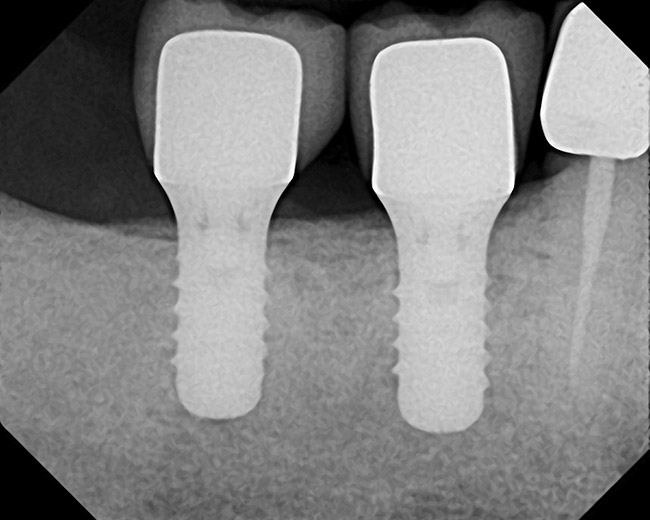

Approximately 18 weeks following extraction and grafting, full-thickness flaps were reflected, revealing complete osseous regeneration of the original defect (Figure 8). The osteotomy was initiated with the same trephine bur to harvest a core of representative bone present at the site of implant insertion. Implant placement proceeded without alteration from the manufacturer's protocol by inserting a 4.8-mm x 8-mm fixture with primary, tactile, stability, and transmucosal healing properties. At about 8 months postplacement, the implant was restored with a custom abutment and cement-retained crown (Figure 9).